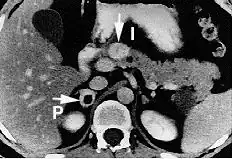

An image of a patient with pheochromocytoma. In patients with this disease, a catecholamine-secreting tumor is formed, and causes excess CNS stimulation, such as excess sweating and tachycardia. Nonselective alpha blockers, such as phenoxybenzamine or phentolamine, can be used to mitigate this disease.

Pheochromocytoma is a disease in which a catecholamine secreting tumor develops.[2][20] Specifically, norepinephrine and epinephrine are secreted by these tumors, either continuously or intermittently.[21] The excess release of these catecholamines increases central nervous system stimulation, thus causing blood vessels to increase in vascular resistance, and ultimately giving rise to hypertension.[20] In addition, patients with these rare tumors are often subject to headaches, heart palpitations, and increased sweating.[2]

Phenoxybenzamine, a nonselective α1 and α2 blocker, has been used to treat pheochromocytoma.[21] This drug blocks the activity of epinephrine and norepinephrine by antagonizing the alpha receptors, thus decreasing vascular resistance, increasing vasodilation, and decreasing blood pressure overall.[21]